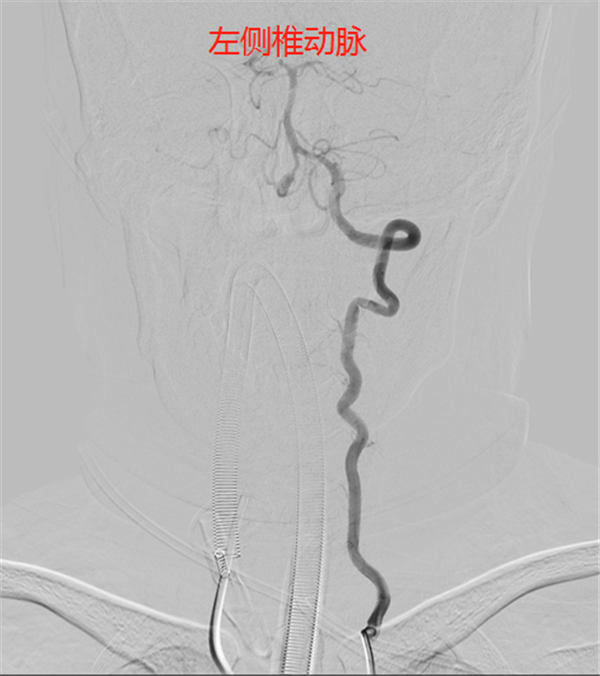

进一步的头颈CTA检查(如下图)证实了上述结论——谢女士的右侧椎动脉v4段长了一颗直径超过7mm的动脉瘤。虽然动脉瘤不属于肿瘤,但却存在破裂出血的致命危险。由于先天异常或后天损伤等因素,颅内动脉血管壁变薄甚至损坏,在源源不断的血流冲击下,就会形成一个突出的动脉瘤。它就像气球一样,在血流作用下可能越来越大,甚至破裂,导致颅内大出血甚至死亡,所以动脉瘤常常被比喻为“不定时炸弹”。

后对全脑血管进行造影,显示——

由于椎动脉属于后循环,管腔内径小,途径迂曲较多,导管到达动脉瘤部位难度较大,加之动脉瘤为梭型动脉瘤,PICA动脉自动脉瘤右侧发出,动脉瘤左侧有一小凸起,怀疑为动脉瘤破裂部位。